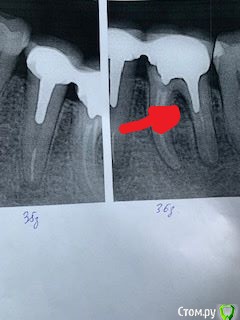

Самарец Опубликовано 30 января, 2020 Поделиться Опубликовано 30 января, 2020 Добрый день! После установки моста на верхних имплантах, антагонисты 35 и 36, после полуторагодовалого отдыха без нагрузки стали сопротивляться.Проявлялось сначала дискомфортом после поедания твердой пищи. В настоящее время - образовался свищ в верхней части десны в районе 36 зуба. На приеме у доктора - промыли, заложили лекарство и вроде все успокоилось. Проблемное место - указано стрелкой в корне 36 зуба. Опухлость десны прошла. Думаю что это все временно. После консультаций у докторов при обострении предлагаются 3 варианта:1. Откинуть лоскут в районе 36 зуба и прочистить проблемное место с лекарством. 2. Разъединить коронку 35 от 36 зуба, удалить 36 зуб и через 2 месяца вкрутить имплант. Коронку 35 зуба обточить.3. Выдернуть 35 и 36 и после заживления вкрутить 2 импланта (это мое предположение) . Посоветуйте пожалуйста уважаемые господа что бы вы рекомендовали в данной ситуации? Заранее благодарю!P.S. Коронке около 14 лет. Ссылка на комментарий